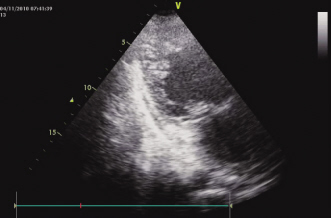

图1 腹部增强CT提示多发脾梗死图2 超声心动图心尖长轴切面显示左室下壁心尖部多量肌小梁及小梁隐窝 【病例摘要】患者,男性,18岁